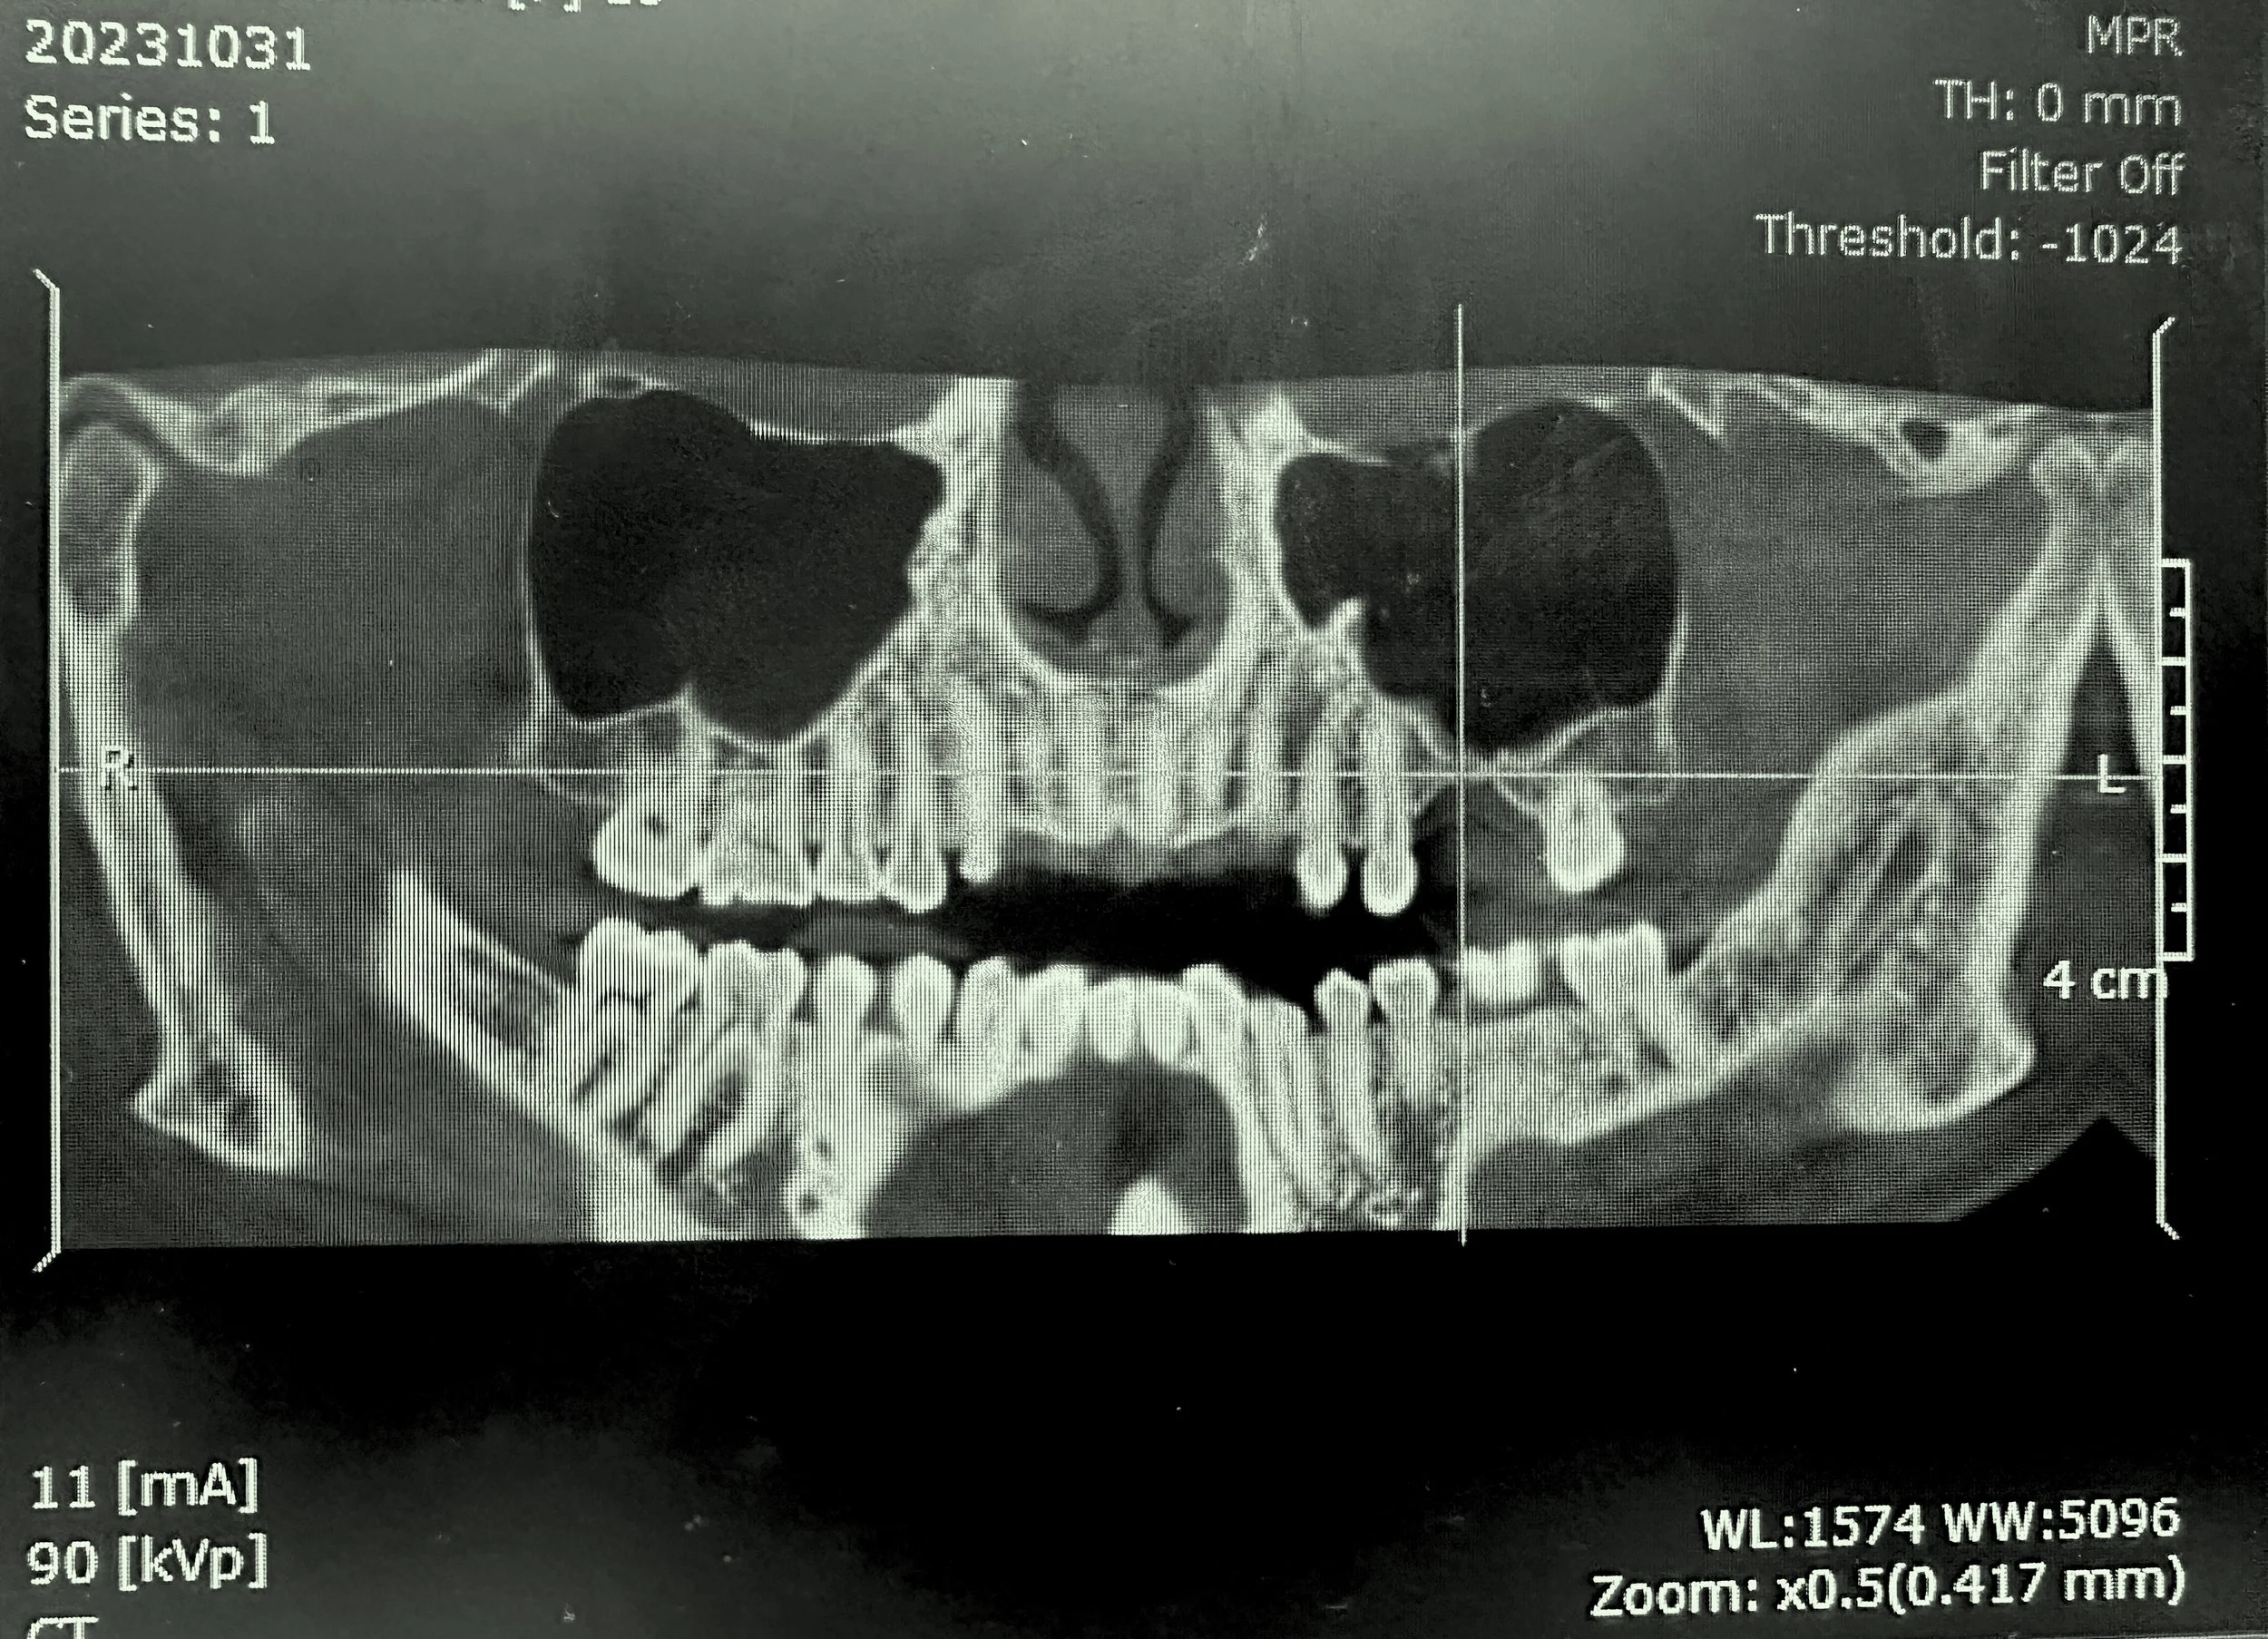

Case Highlight: #14 Surgical Extraction, Ridge Preservation, and Sinus Augmentation

Case Highlight: Lateral Window Sinus Lift — Tooth #14